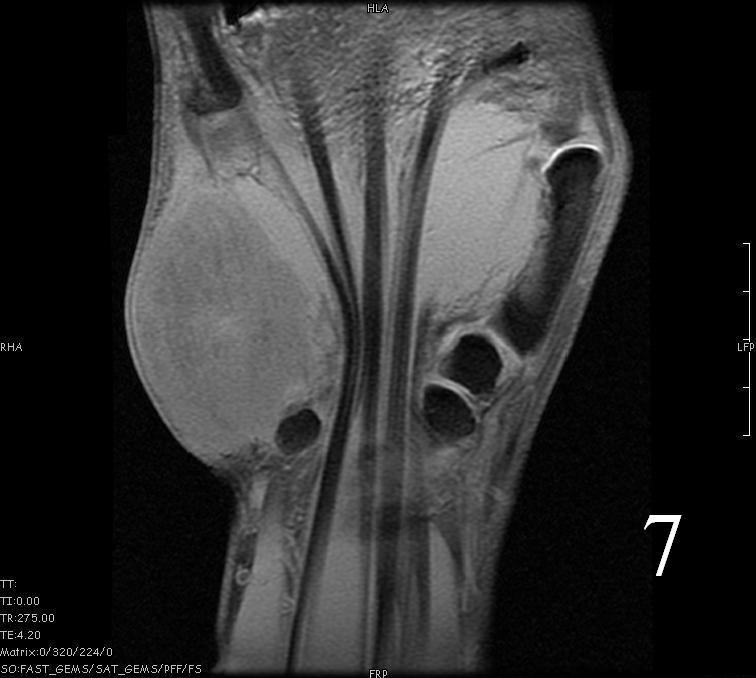

- Isointense to skeletal muscle on T1 (Fig. 4, Fig. 5, Fig. 7, Fig. 8)

Fig. 4-9: MRI of a rhabdomyosarcoma of the hand. The MRI is nonspecific and shows a heterogeneous mass particularly on postgadolinium images T1 W images (Fig. 8) and T2 W images (Fig. 9).